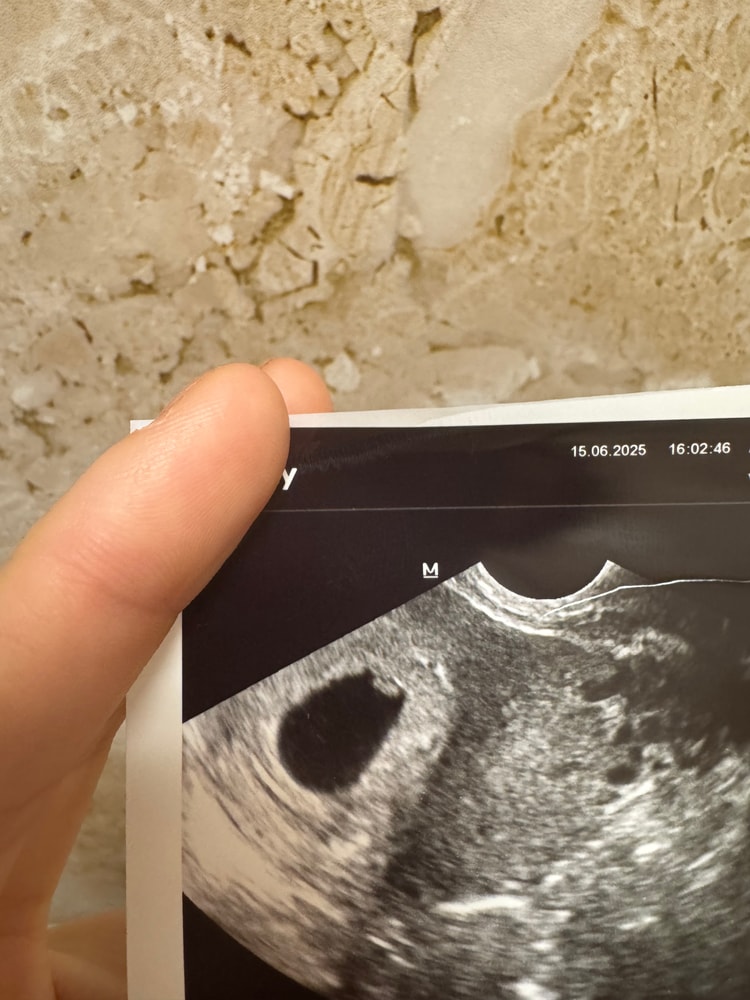

Пол малышаНа бб девочки часто создают посты по поводу раннего определения пола-метод Рамзи и ведь часто у них совпадает, девочки как думаете кто в теремочке живет уже так любопытно🙈

Если узи трансвагинально делали, то я напророчу вам мальчика. Сама этим методом заинтересовалась в Б, изучала его, интересно было. У меня совпало. Метод имеет погрешность 3%, но плюс к тому его ещё часто неверно трактуют- сроки не соблюдают (до 8 недель, позже неинформативно), путают метод узи (по животу или вагинально). По моим данным если узи до 8 недель выполнено трансвагинальным датчиком, то прикрепление слева - мальчик, справа - девочка. Абдоминально - наоборот. А желаю вам девчуху для разнообразия 😃

Скажите пожалуйста, кто у меня?